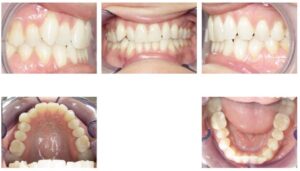

Case 3 – Attachments on UL1, U2s, L2s and L3s

| Initial | 6-month progress, 22 aligners |

![]() | ![]() |